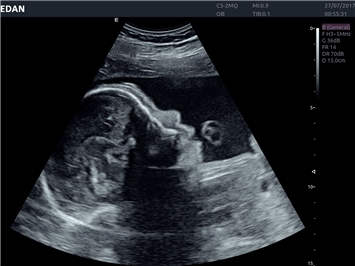

EDAN Acclarix LX4 представляет собой инновационную ультразвуковую систему, построенную на усовершенствованной платформе Acclarix. Сочетание высокого качества визуализации с интеллектуальным рабочим процессом делает эту систему оптимальным выбором для клиник, ценящих эффективность и экономичность.

• Автоматизированные измерения в акушерстве

• Акушерства и гинекологии

Гинекология:

Да